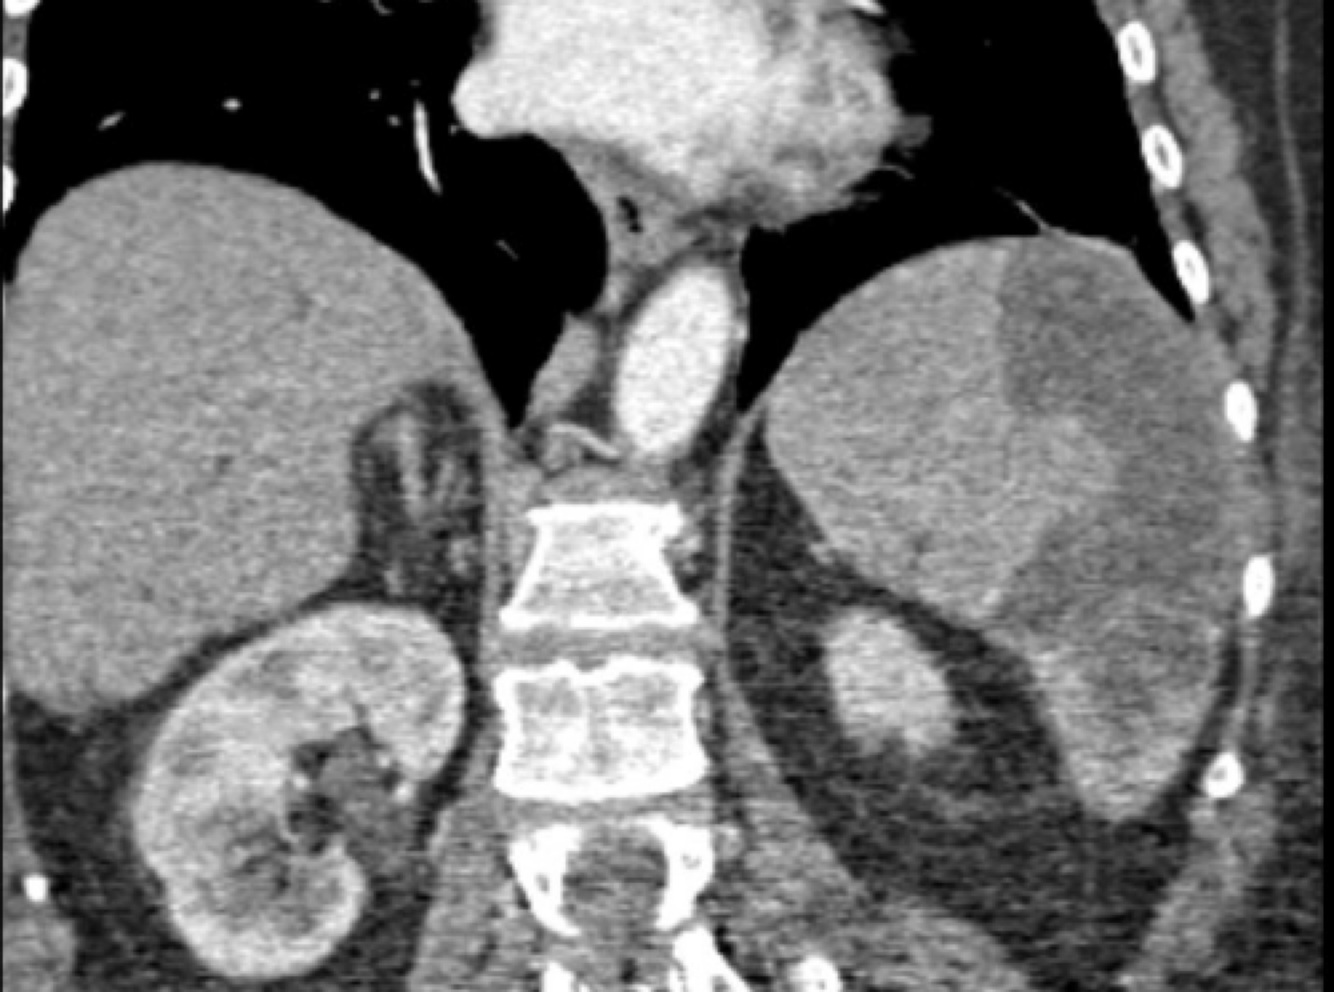

splenic infarct:

The image on the left demonstrates an enlarged spleen